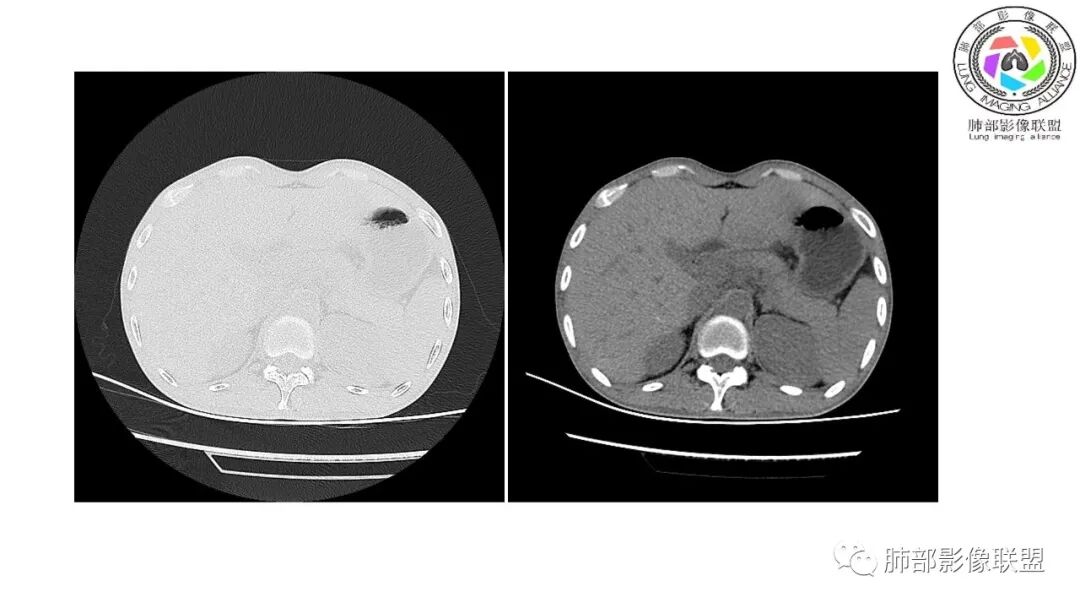

影像与临床:1.青年男性,HlV阳性,颜面部皮疹(未提供皮疹图像)、发热(高热),实验室CRP、PCT高,T-Spot阴性。2.右肺下叶空洞结节,壁厚不均,边界清楚,其内线状影,未见液平及钙化,未见卫星灶,纵隔淋巴结增大,双侧腋窝见增大淋巴结。心腔内低密度提示贫血可能。肝脾影增大,未见结节影及块影。腹膜后见多发增大淋巴结。

综合分析:本例肺部影像学改变并不具有特征性,空洞性病灶须与多种疾病鉴别,但年轻HIV阳性患者,高热,皮疹,肝脾增大,纵隔、腋窝、腹膜后见多发增大淋巴结等都强烈提示马尔尼菲篮状菌感染的可能性。

马尔尼菲青霉菌病(Penicilliosis Maneffei,PSM) 是由马尔尼菲青霉菌(Penicillium Mane&i,PM)感染引起的一种致死性深部真菌病,PM主要侵犯单核巨噬系统,可表现为局灶性和播散性感染,在免疫功能低下的感染者中,死亡率高。该菌是由Capponi1956年从越南野生中华竹鼠肝脏中首次分离出并命名。该病主要流行于东南亚一带,在我国以广西广东多见。有文献研究中国大陆1984年到2009年感染马尔尼菲青霉菌668例患者中有99.4%病例发生在中国南部,以广西广东为主,有87.7%病例发生在艾滋病患者中,有3.8%的病人发生在其它免疫抑制患者中,有8.5%发生在免疫功能正常者。PM的传播途径尚不明确,公认的主要传播途径有呼吸道,消化道,外伤等,亦不除外接触孢子污染的土壤而感染。马尔尼菲青霉菌病的常见的临床表现为发热,贫血,消瘦,呼吸道症状,皮肤损害,肝脾肿,淋巴结肿大。播散型PSM常累及肺,皮肤,网状内皮系统(包括骨,骨髓,关节,淋巴结,心包,肝脾)。不同宿主状态下PSM临床表现也有不同,HIV阳性患者主要表现为持续性发热,软疣状皮肤损害,血培养阳性率高,白细胞正常或偏低等。HIV阴性患者主要表现为间歇发热,皮下结节和脓肿,淋巴结肿大,骨痛溶骨,白细胞增高等。马尔尼菲青霉病的诊断主要靠沙氏琼脂培养基25℃及37℃环境下可培养出PM(金标准)。马尔尼菲青霉菌肺部表现具有多样性,可以表现为实质改变、间质改变、纵隔淋巴结肿大、胸膜改变及气管改变。有文献报道马尔尼菲青霉菌病患者82.7%胸部CT有异常改变,胸部CT表现:45.6%患者肺野斑片状浸润阴影或局限性肺实变,11.9%患者表现为结节影,11.5%患者表现为毛玻璃改变,8.4%患者表现为弥漫性粟粒样病变,5.3%患者表现为结节状肿块影。45.1%患者胸部影像学伴肺门或纵隔淋巴结肿大,23.5%患者伴胸腔积液,8.0%伴空洞病灶。参考文献:张建全, 杨美玲, 钟小宁, 等. 人免疫缺陷病毒抗体阴性与阳性者播散性马尔尼菲青霉菌病的临床及实验室特征[J]. 中华结核和呼吸杂志, 2008, 31(10):740-746.张云桂,赵月娟,李玉叶,等.226例艾滋病合并马尔尼菲青霉菌病患者的影像学特征[J]. 皮肤病与性病,2016, 38(2):91-94.